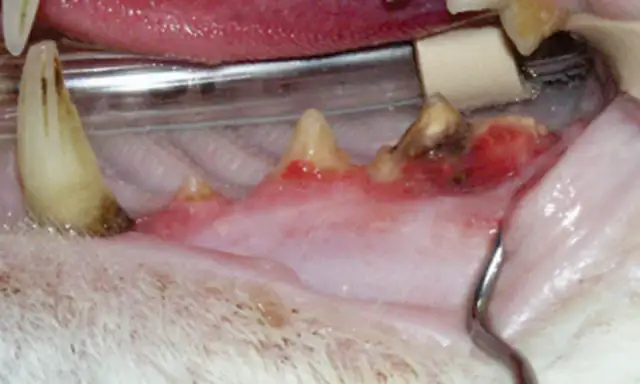

The following images show full-mouth tooth extraction in the maxillary quadrant of cats.

FIGURE 1

Right maxillary arcade with the patient in dorsal recumbency. Extraction of all teeth was recommended to treat periodontal disease and tooth resorption.